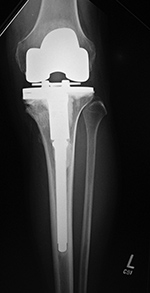

Cruciate retaining total knee arthroplasty (TKA)   Biomet Vanguard 360 Revision Knee System

Cruciate retaining TKA Cruciate retaining TKA Biomet Vanguard 360 knee revision Biomet Vanguard 360 knee revision

68 year-old woman treated for severe left knee osteoarthritis This replaced a loose prior total knee arthroplasty. The patellar button was left in place. A surgical drain is in place, and there is subcutaneous gas from the recent surgery.